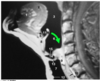

larynx

- part of the respiratory system between the pharynx and the trachea

- is a complex organ of voice production, lies in the anterior part of neck at the level of the bodies of C3-C6 vertebrae

- functions

- for the passage of air toward and from the lungs

- to prevent foreign objects from entering lower respiratory passages

- in phonation/voice production